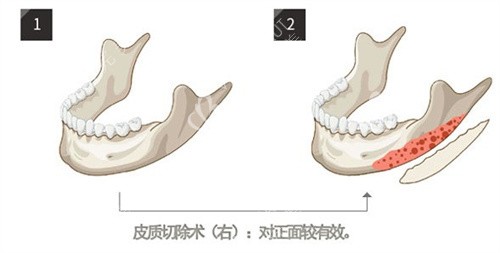

小切口与小创口处理理念

他采用特有内推调整技术进行操作。手术入口小且剥离范围控制更准。减少组织创伤从而降低痛感。术后多数无需佩戴头套压迫。

如何处理复杂修复病例

李运峰在处理失败手术病例上有经验。采用定制人工骨进行轮廓修复。实现骨骼衔接自然和面部流畅。技术能力得到同行认可。